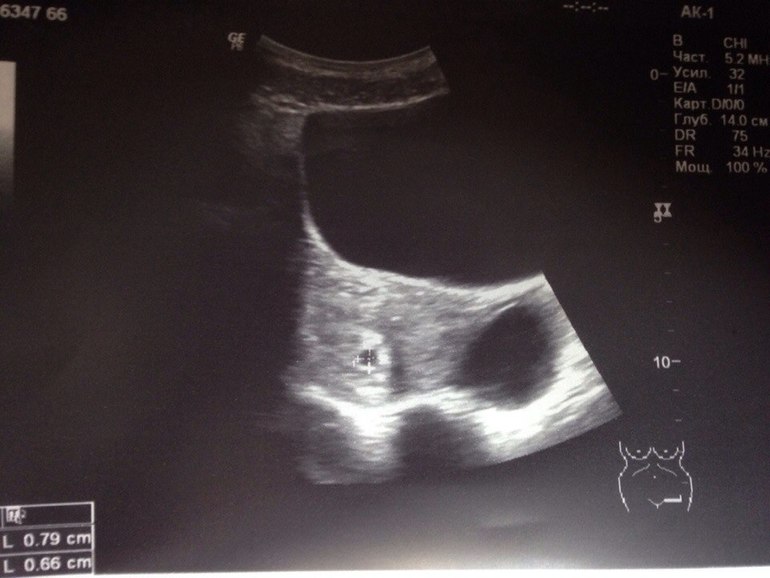

Пришла на первое узи, сегодня по акушерскому сроку нам 5 недель и 3 дня, врач увидела только плодное яйцо и совсем не увидела эмбриона((Диагноз под вопросом, что у меня неразвивающаяся беременность...ХГЧ сдавала в пятницу - был 1600, за неделю до этого ХГЧ был 43.

Какая еще замершая, Вы чего? Нет там никакой замершой, вполне в норме размеры Вашего пя для такого срока.